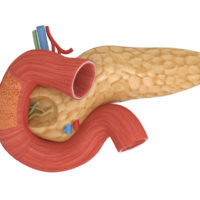

Mindegyik faj által szintetizált bizonyos sejtek. A glukagon felelős alfa-sejtjeinek az inzulin - a béta-sejtek, és a generációs szomatosztatin részt delta-sejtek. A szerkezet a endokrin sejtek a hasnyálmirigy szekretálnak lehetővé teszik kívánt anyagokat közvetlenül a hajók.

Mi az a struktúra, és ahol a hasnyálmirigy emberben

Biomarkerek Hasnyálmirigy: méret (normál felnőtt)

Funkció és a betegség a hasnyálmirigy